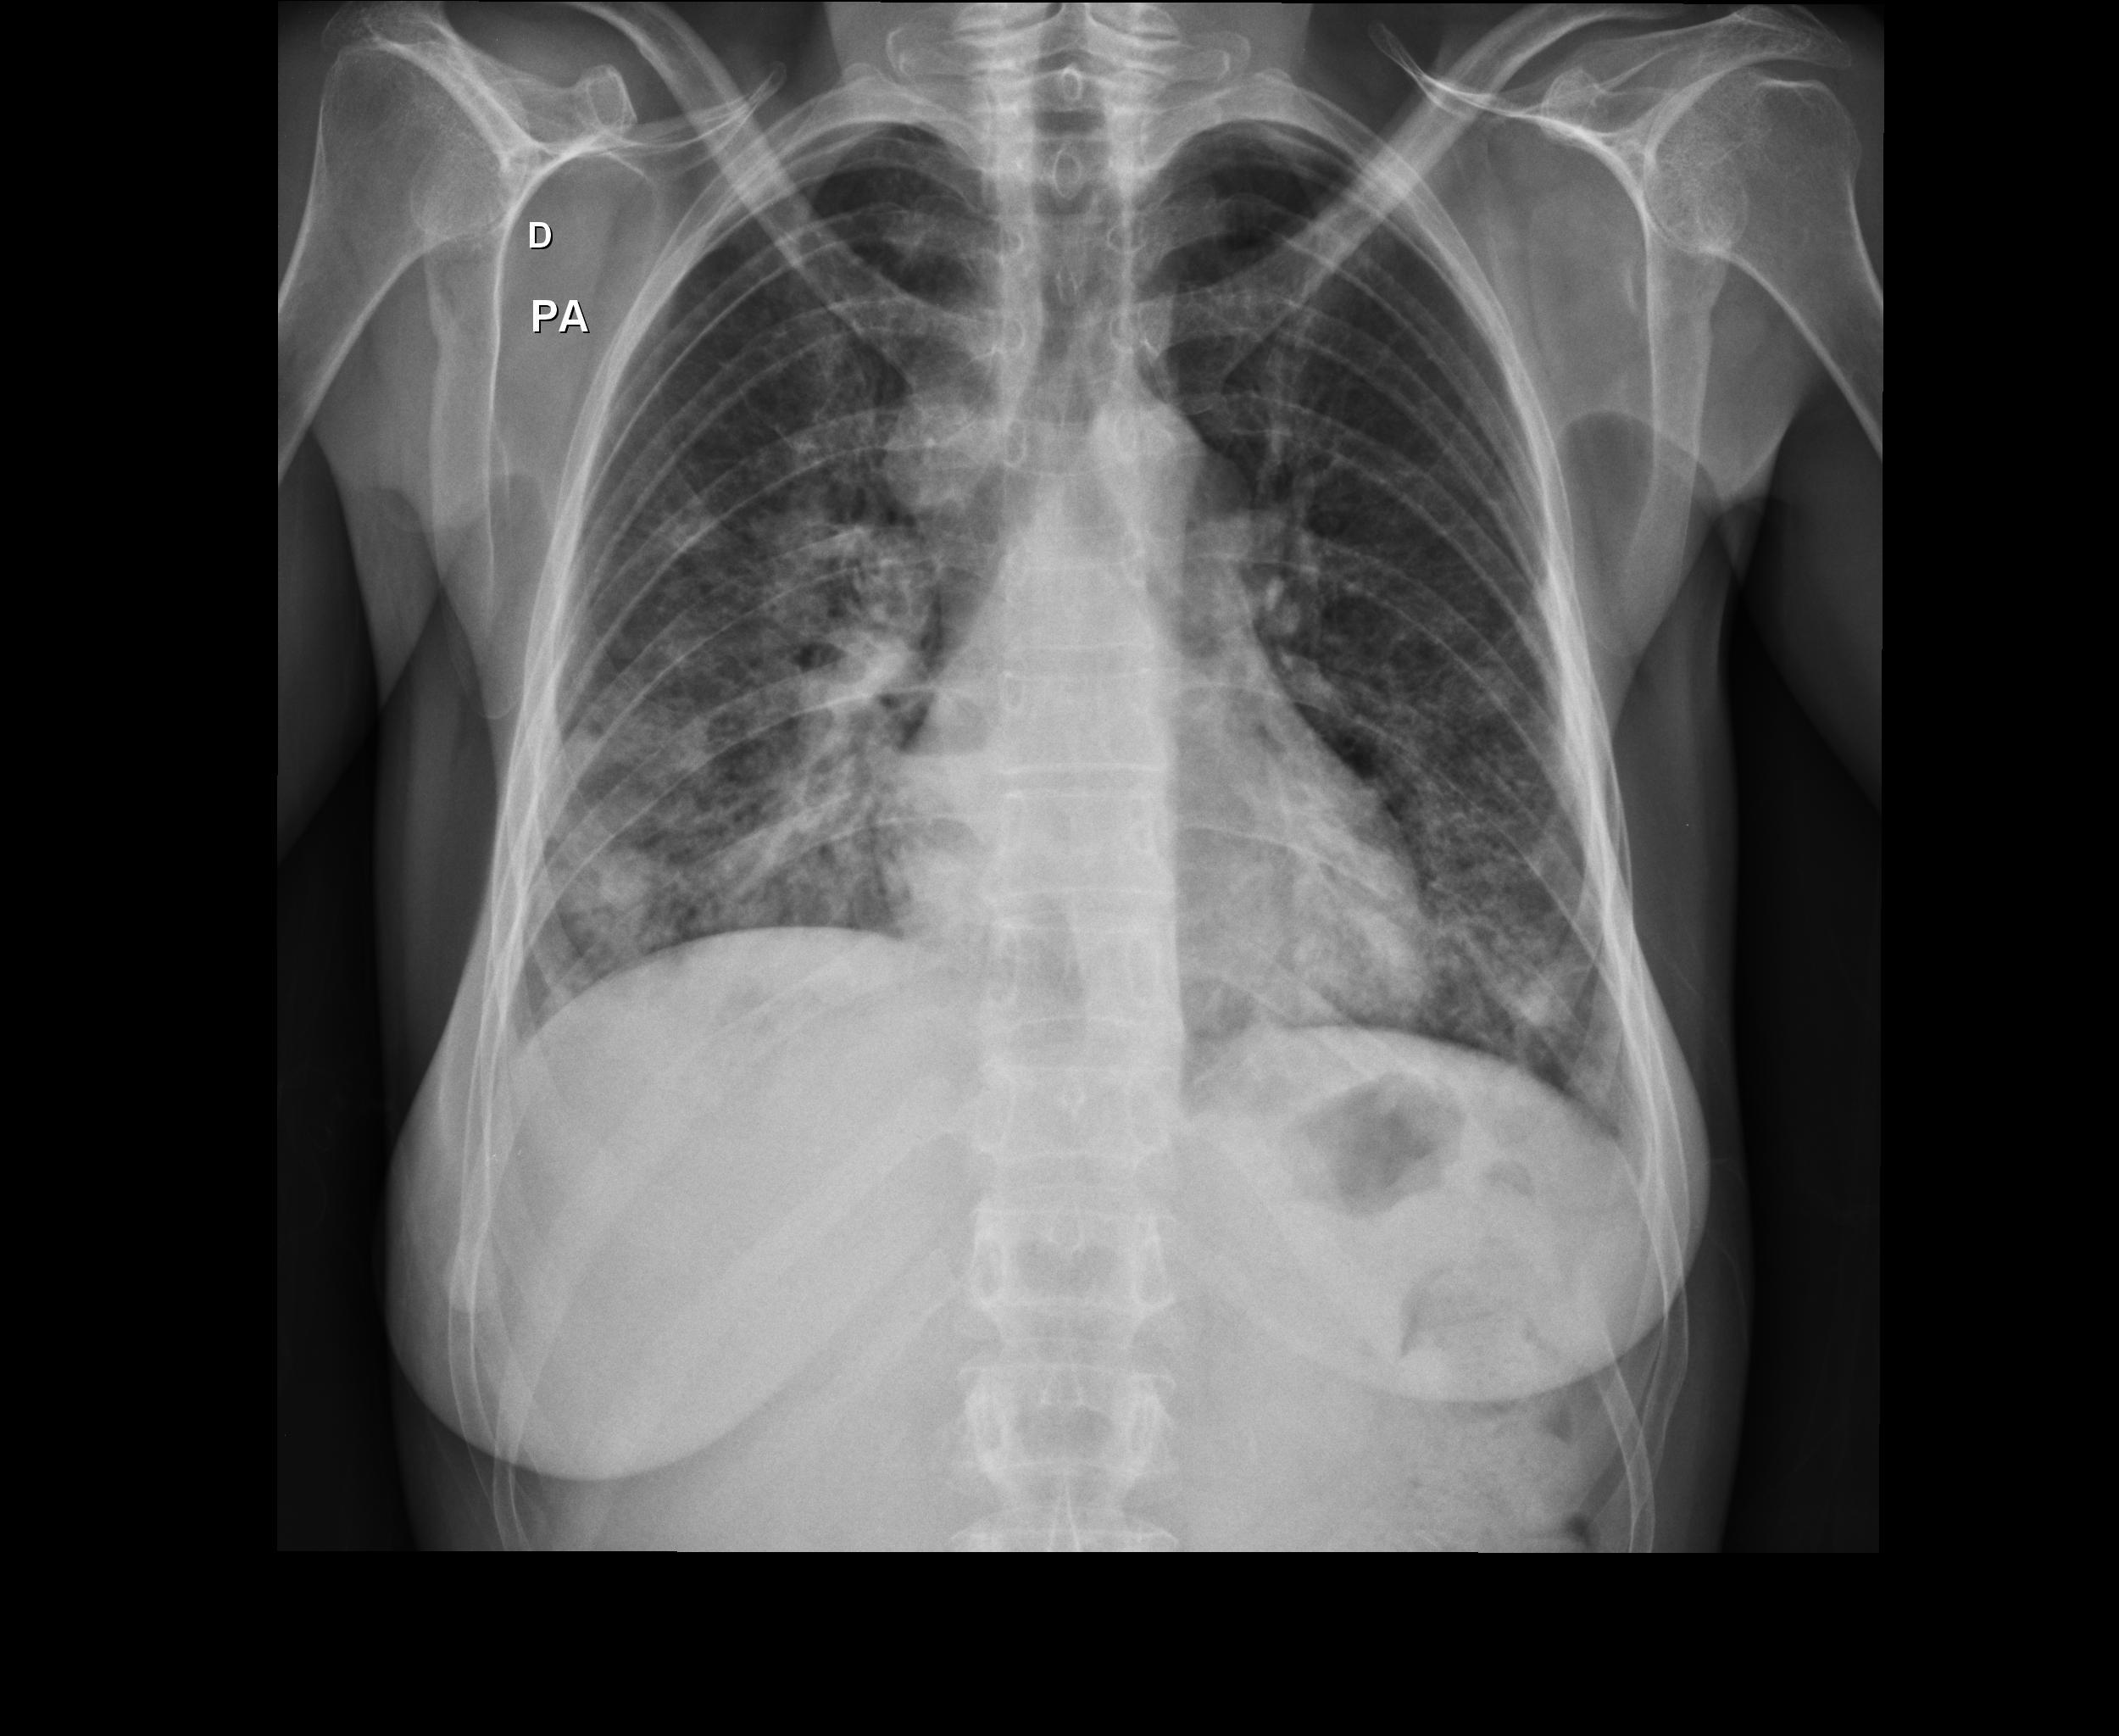

Caso relatado na Reunião de Discussão de Casos Clínicos do Hospital Universitário Prof. Polydoro Ernani de São Thiago, iniciada pelos Profs. Jorge Dias de Matos, Marisa Helena César Coral e Rosemeri Maurici da Silva, em julho de 2017. No dia 14 de junho de 2018, no auditório do HUPEST, realizou-se a apresentação e discussão do caso cujo registro é apresentado a seguir. Trata-se da discussão de onze casos em radiologia torácia, de forma interativa com a plateia, e assim ocorre também neste artigo.